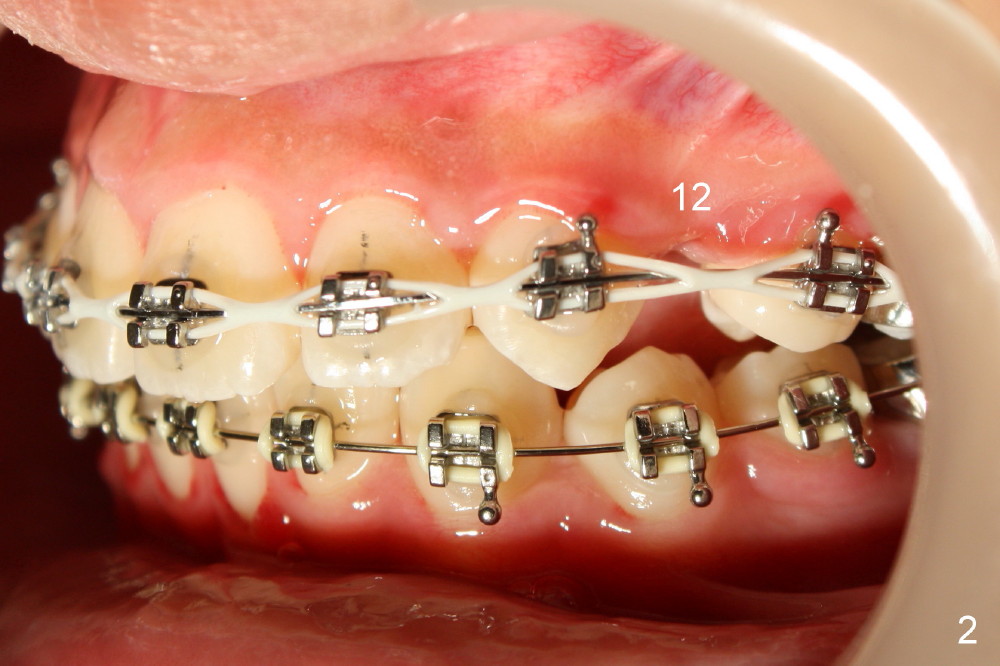

Power chains are used to close the extraction spaces (Fig.2).